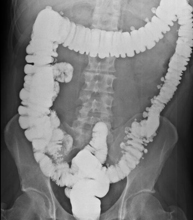

Prova diagnòstica que consisteix en obtenir imatges radiològiques de l'intestí gros (còlon i recte) mitjançant l'ús de raigs X. S'utilitza un contrast opac que s'administra a través del recte en forma d'ènema i també s'introdueix aire per expandir el còlon.